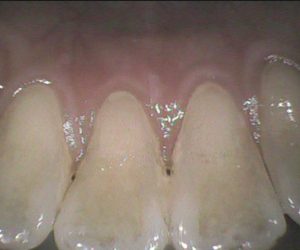

今日のクリーニングです。     クリーニング前   この方は約3年ぶりのクリーニングで、 下の前歯の間から根元にかけて歯石が多くついていました。   クリーニング後   […]